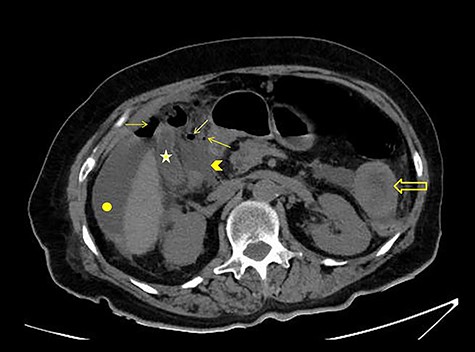

The patient was afebrile but hemodynamically unstable, with 115 bpm and a systolic pressure of 80 mmHg on presentation. Clinical examination revealed abdominal distension, diminished bowel sounds and severe tenderness with peritoneal signs in all of the abdominal quadrants. Her laboratory blood examination showed elevated number of neutrophils (7.77 K/μl), elevated C-reactive protein value (82.46 mg/dl) and decreased Na+ (119 mEq/l). After initial resuscitation, a computed tomography (CT) scan was performed. It showed free abdominal air and fluid in the peritoneal cavity, indicating an intestinal perforation (Figs 1–3).

CT scan without intravenous (iv) and oral (per os) contrast media administration: The disruption of lumen continuity at the level of duodenum bulb with presence of fluid (arrow head) and free air (arrows). There are also presence of free fluid in subdiaphragmatic space (dot) and edema in jejunum wall (open arrow). Contracted gallbladder is noted by star.